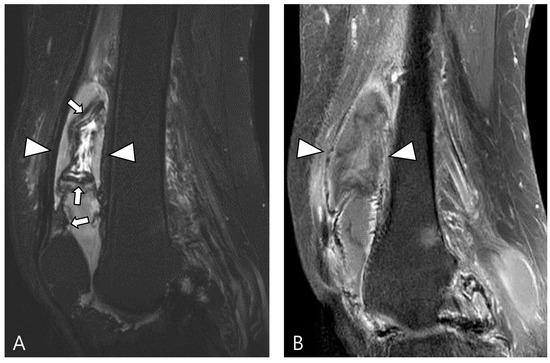

2.4. Relationship to Adjacent Structures of D-TSGCT

3.2. Differential Diagnoses of Extra-Articular D-TSGCT